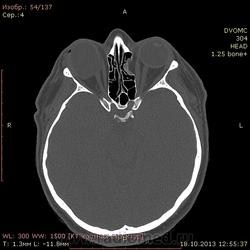

52 года. По направлению от невролога после травмы от 13.10. Правый глаз - посттравматические изменения(травма в детстве).

Интересует ваше мнение по поводу медиальной стенки левой глазницы - что за дефект? чего-то растет или последствия старой травмы или вариант нормы?

Или стенка все-таки без дефекта, а просто таким образом деформирована?

Считаю, что слева - это последствия "старой" травмы, т.н. взрывного (blowout) перелома медиальной стенки орбиты.